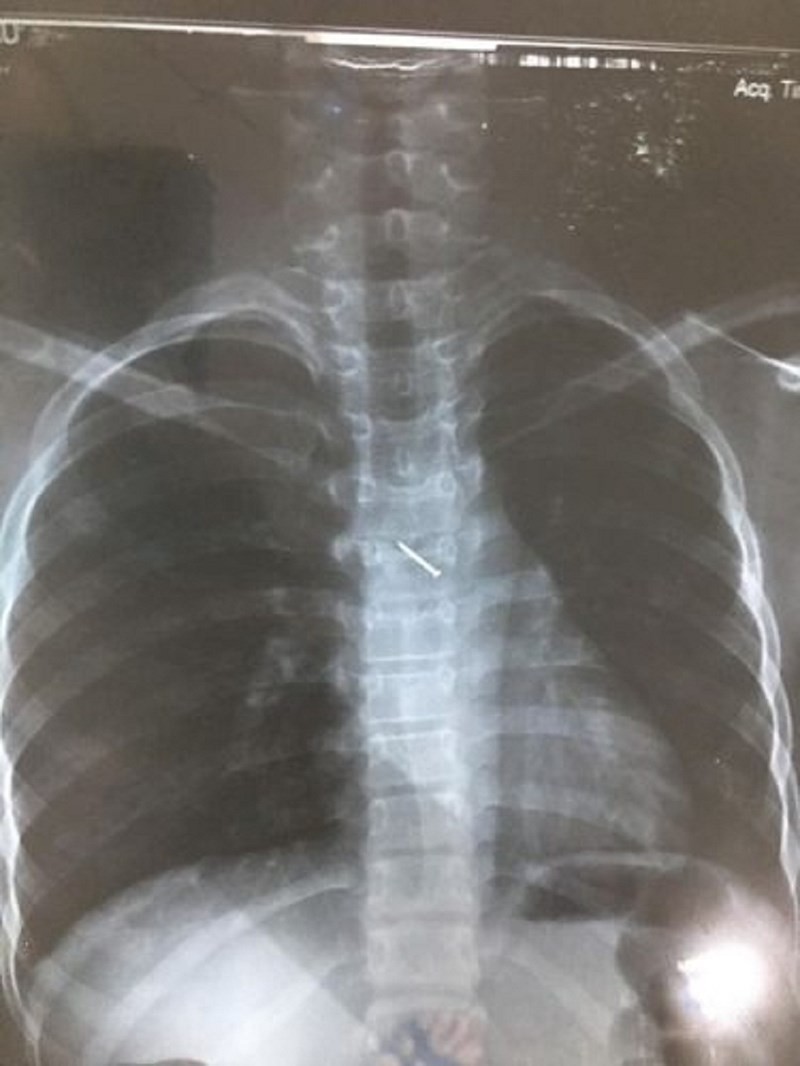

Sau sự cố, bé ho sặc sụa, khạc ra máu, nôn nhiều nên được người nhà đưa đến bệnh viện đa khoa Mộc Châu (Sơn La) khám. Tại đây, qua chụp X-quang các bác sĩ xác định lồng ngực bệnh nhân có dị vật hình đinh ghim. Bệnh nhân được chuyển tới BV Nhi Trung ương để theo dõi và tiếp tục điều trị.

Tại BV Nhi Trung ương, hình ảnh chụp X-quang cho thấy có dị vật là một chiếc đinh ghim dài khoảng 1,5cm nằm ở vị trí thành ngực của bệnh nhân. Các bác sĩ đã hội chẩn và quyết định phẫu thuật nội soi lấy dị vật.

Ca phẫu thuật nội soi gắp dị vật được tiến hành ngay trong buổi chiều ngày 18-5. Sau hơn 10 phút làm thủ thuật, các bác sĩ đã lấy ra được một chiếc đinh ghim bằng sắt dài 1,5cm.